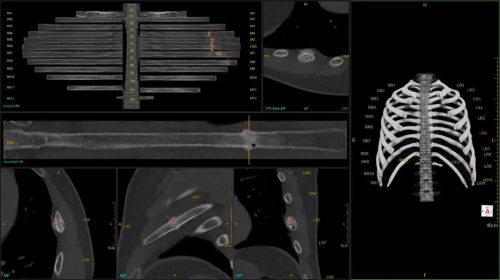

在创伤急救方面,无极系列CT实现了业内独有的16cm探测器全覆盖的螺旋扫描。相较于常规8cm螺旋扫描,该技术可缩短扫描时间50%以上,不仅大幅提高了扫描效率,还能有效抑制各类运动伪影,为创伤患者救治提供有力支持。

16cm螺旋胸腹盆1s级快扫

创伤骨折辅助分析